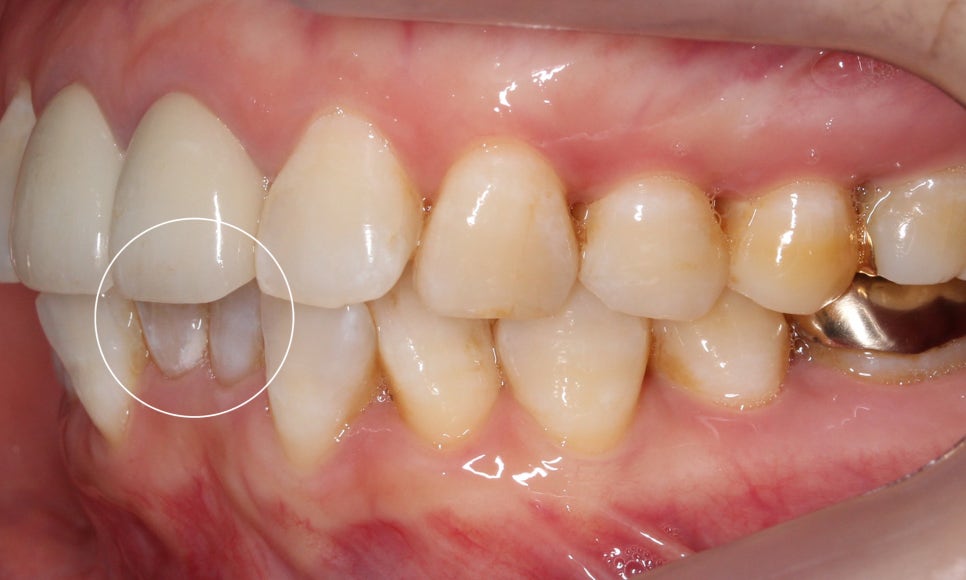

측면의 모습을 보면 아랫니의 앞쪽이

윗니의 뒷쪽으로 많이 들어가 있는 것을

확인할 수 있습니다!

반대쪽도 같은 모습인데요,

이렇게 아랫니가 윗니를 향해

깊숙히 물린다면 아랫니의 절단연에 의해

윗니의 잇몸이 상처를 입을 수 있습니다.

윗니는 아랫니에 비해

비교적 가지런한 모습이죠?

+앞니(중절치)가 약간 불투명하고

잇몸 부분이 까맣게 보이는 것은

보철치료를 진행하셨기 때문입니다!